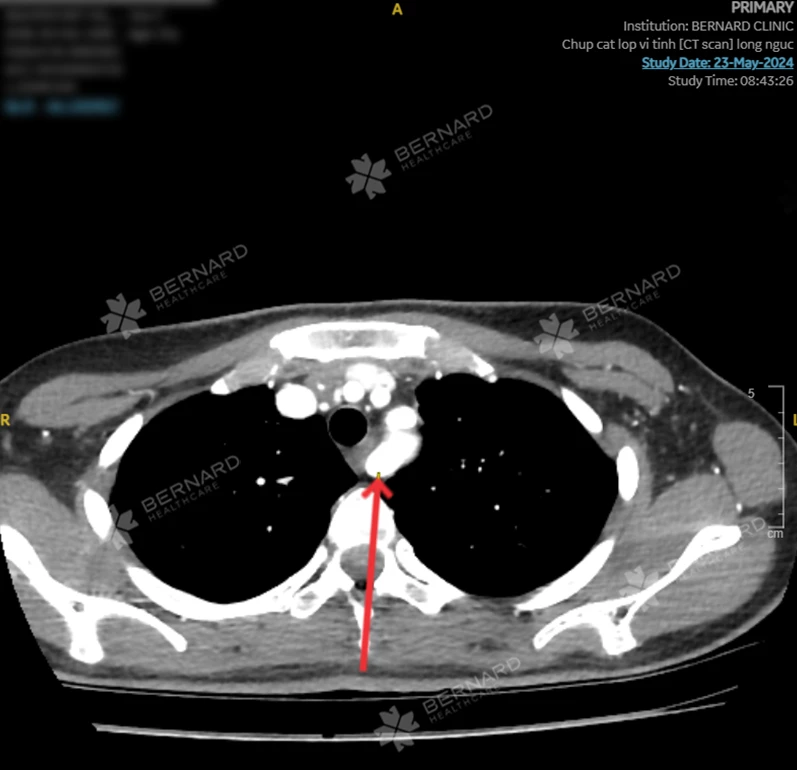

Bên cạnh đó, các bác sĩ Bernard cũng kịp thời phát hiện một tình trạng hiếm gặp khác mà chị V.H. mắc phải là Động mạch dưới đòn phải lạc chỗ, dù trước đó chị V.H. không có triệu chứng sức khỏe bất thường.

Động mạch dưới đòn phải lạc chỗ (Aberrant right subclavian artery - ARSA) là một biến dạng hiếm gặp của động mạch, ít gây ảnh hưởng nghiêm trọng đến sức khỏe và thường xuất hiện đồng thời trên những bệnh nhân có các dị tật bẩm sinh tại lồng ngực. Do đó, bệnh nhân cần duy trì thói quen kiểm tra sức khỏe định kỳ để theo dõi và nắm rõ tình trạng sức khỏe.